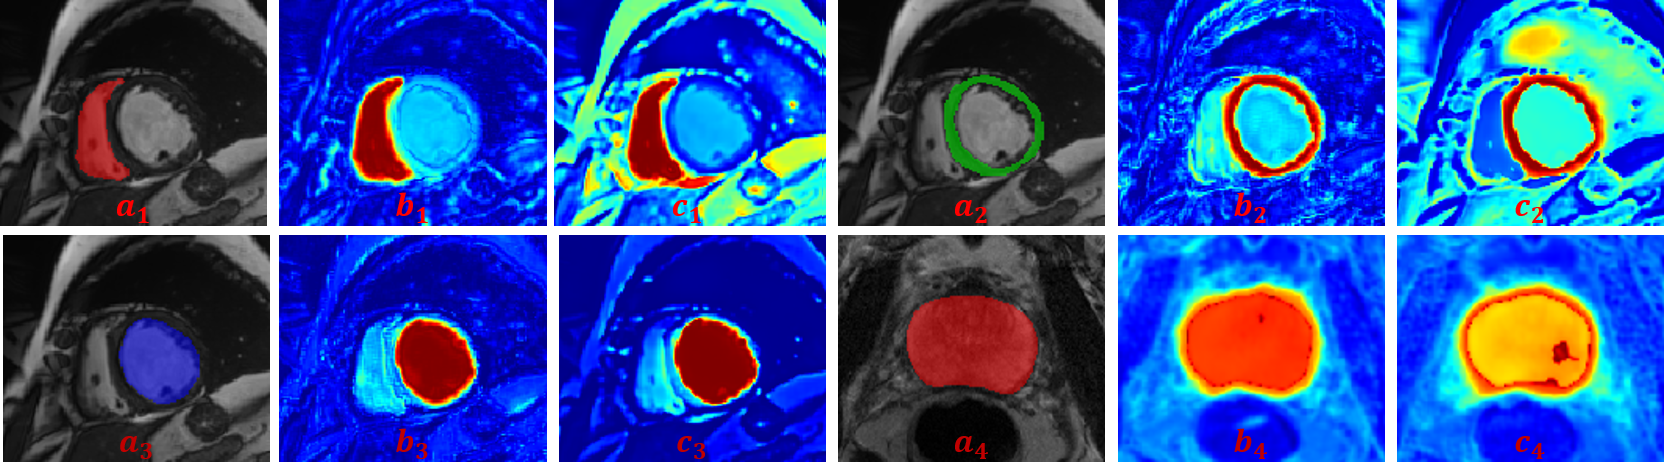

Refer to caption

Figure 3: Visualized results for prototypical probability predictions for RV, Myo, LV, and prostate class: (a) Ground truth, (b) Self-aware probability prediction, p^kksubscript^𝑝𝑘𝑘\hat{p}_{kk}, (c) Cross-aware probability prediction, p^kosubscript^𝑝𝑘𝑜\hat{p}_{ko}.

Ablation Study. To demonstrate the effectiveness of the key design of SCP-Net, we perform ablation study on PROMISE12 dataset by gradually adding loss components. Table 2 reports the results of ablation results. It can be observed that both the design of SPCC and CPCC promote the semi-supervised segmentation performance according to the first three rows, which demonstrates that PCC extracts valuable information from the image itself and other images, making them well-suited for semi-supervised segmentation. We also visualize the prototypical prediction p^kksubscript^𝑝𝑘𝑘\hat{p}_{kk} and p^kosubscript^𝑝𝑘𝑜\hat{p}_{ko} for different structures in Fig. 3. These predictions are consistent with the ground truths and show intra-class compactness and inter-class discrepancy, which validates that PCC provides effective supervision for semi-supervised segmentation. In the last three rows, the gradually improving performance verifies that the integration of prediction uncertainty w1subscript𝑤1w_{1} and self-aware confidence w2subscript𝑤2w_{2} in CPCC improves the reliability and stability of consistency training.